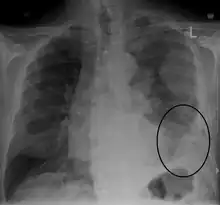

CXR demonstrating a mesothelioma

Diagnosing mesothelioma is often difficult because the symptoms are similar to those of a number of other conditions. Diagnosis begins with a review of the patient's medical history. A history of exposure to asbestos may increase clinical suspicion for mesothelioma. A physical examination is performed, followed by chest X-ray and often lung function tests. The X-ray may reveal pleural thickening commonly seen after asbestos exposure and increases suspicion of mesothelioma.[15] A CT (or CAT) scan or an MRI is usually performed. If a large amount of fluid is present, abnormal cells may be detected by cytopathology if this fluid is aspirated with a syringe.[11] For pleural fluid, this is done by thoracentesis or tube thoracostomy (chest tube); for ascites, with paracentesis or ascitic drain; and for pericardial effusion with pericardiocentesis. While absence of malignant cells on cytology does not completely exclude mesothelioma, it makes it much more unlikely, especially if an alternative diagnosis can be made (e.g., tuberculosis, heart failure). However, with primary pericardial mesothelioma, pericardial fluid may not contain malignant cells and a tissue biopsy is more useful in diagnosis.[11] Using conventional cytology diagnosis of malignant mesothelioma is difficult, but immunohistochemistry has greatly enhanced the accuracy of cytology.